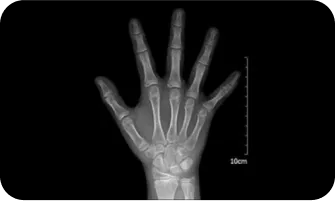

02

엑스레이 검사를 이용한

여아의 골연령검사

300점

400점

8.5세

500점

10세

600점

11세

700점

12세

800점

13 ~ 14세

900점

14 ~ 15세

1000점

15세 ~